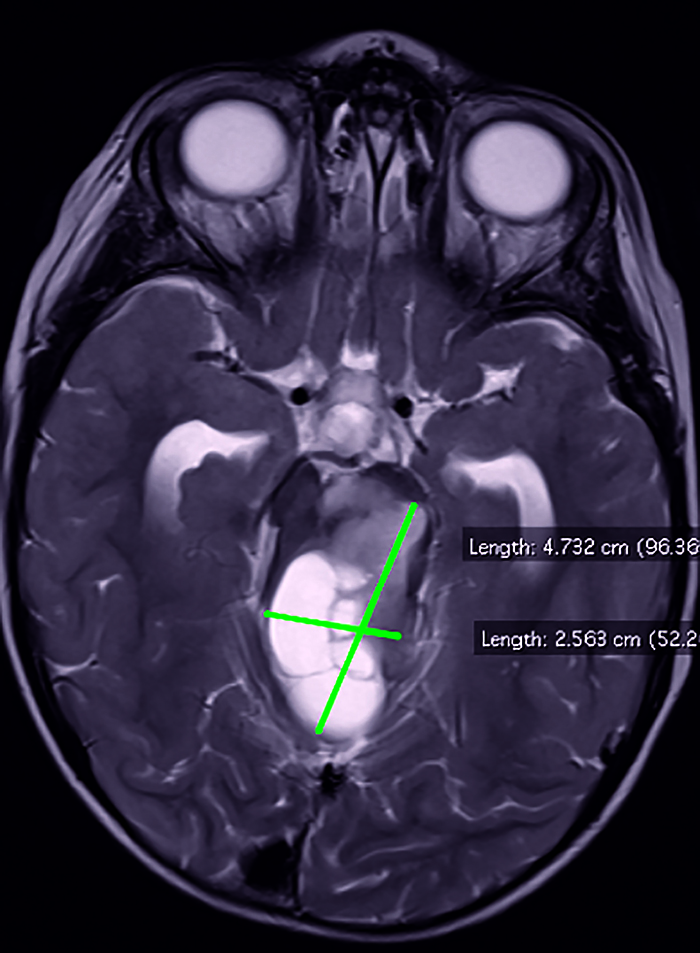

Pacientul I.T., în vârstă de 2 ani și 7 luni, fără antecedente heredocolaterale sau personale semnificative, s-a internat pentru asimetrie facială remarcată de la naștere, asociată cu laterocolis drept. Anterior cu o lună față de internarea curentă a fost evaluat neurologic, fiind observat un frust deficit la nivelul hemicorpului drept. La internare, examenul clinic a fost normal. Examenul neurologic a evidențiat pareză facială dreaptă de tip central și frustă hemipareză dreaptă. S-a efectuat IRM cerebral cu substanță de contrast, ce a evidențiat o formațiune tumorală, posibil astrocitompilocitic la nivelul trunchiului cerebral (figurile 1 și 2).

Figura 1. IRM cerebral secvență T2 ponderată, secțiune transversală, formațiune tumorală la nivelul trunchiului cerebral (imagine din arhiva secției de Neurologie Pediatrică a Spitalului de Copii „Dr. Victor Gomoiu” București)